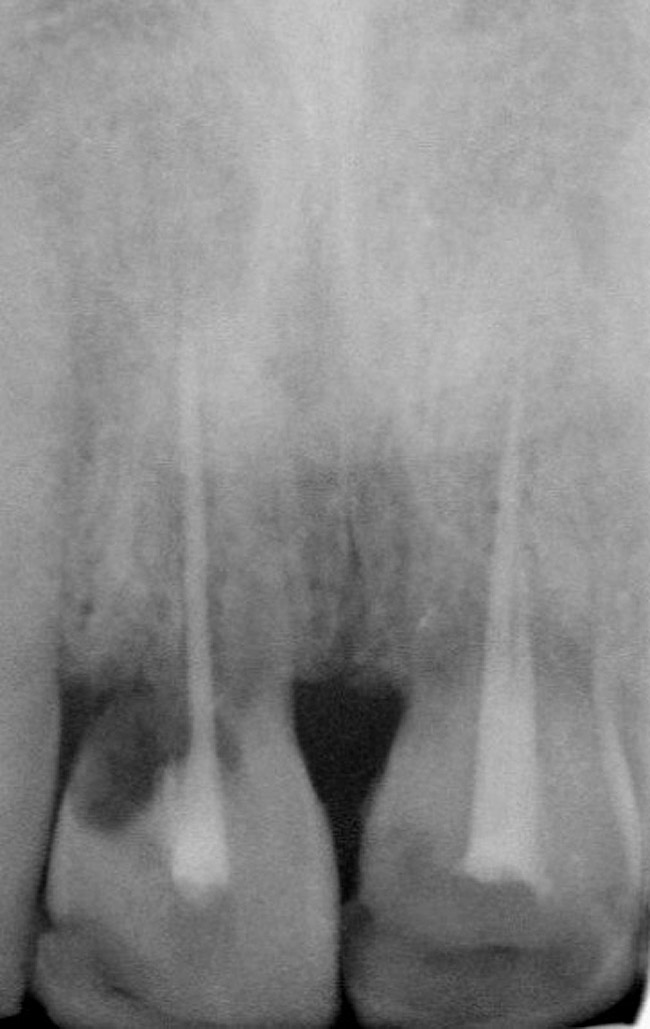

Figure 1  Initial presentation. Teeth Nos. 8 and 9 had internal and external resorption and were deemed hopeless. Recession of 4 mm was associated with tooth No. 9

Figure 1